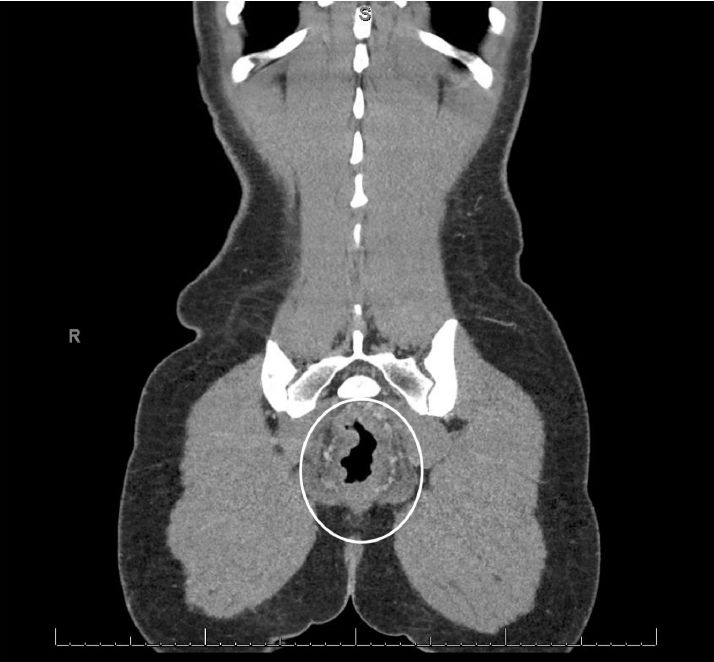

HIV和粪便检查结果为阴性。腹部和骨盆的计算机断层扫描(CT)扫描提示了异常发现(图A,图B),因此,我们又用内窥镜对患者进行了检查。在接下来的几天,乙状结肠镜检查的结果如图C、图D和图E。

图B

腹部和骨盆的CT显示直肠壁增厚,提示直肠的炎症和充血,即直肠炎(图A,B)。乙状结肠镜检查的结果显示直肠和远端乙状结肠内的粘膜严重充血,伴随弥漫性红点(图C,D)与表面渗出物,且直肠和乙状结肠远端的粘膜脆弱。这些发现与化学直肠炎,特别是过氧化氢诱导的化学直肠炎的表现一致。